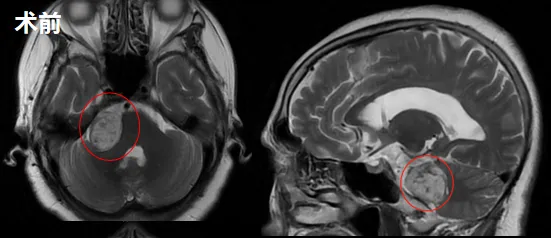

巴教授为他示范手术,术前术后影像对比